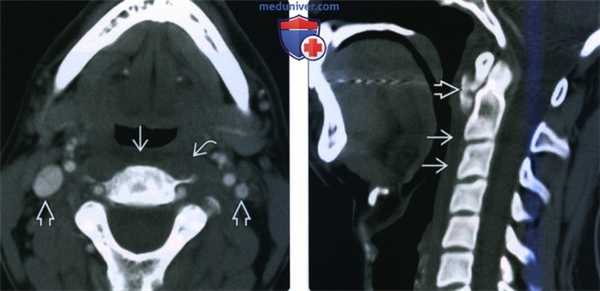

(Слева) КТ с КУ, аксиальная проекция. ЗГП расширено за счет наличия в нем жидкостного содержимого низкой плотности, которое не накапливает контрастное вещество. Контуры предпозвоночных мышц и глотки четкие. Обратите внимание на реактивный шейный лимфаденит с двух сторон характерный для стрептококкового фарингита.

(Справа) КТ с КУ, сагиттальная проекция. У пациента с тонзиллитом также наблюдается отек ЗГП. Контраст в заглоточном пространстве не накапливается. Обратите внимание на увеличенную глоточную миндалину, плотность которой понижена. В гортаноглотке, кпереди от выпота, имеется газ.